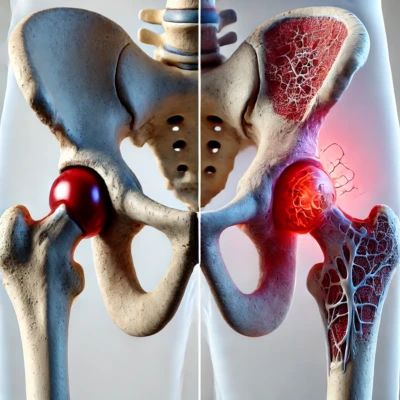

- Artroscopia: accesso mini-invasivo con artroscopio tramite piccole incisioni.

- Artroplastica: sostituzione protesica di un’articolazione.

- Malattie degenerative (es. artrosi).